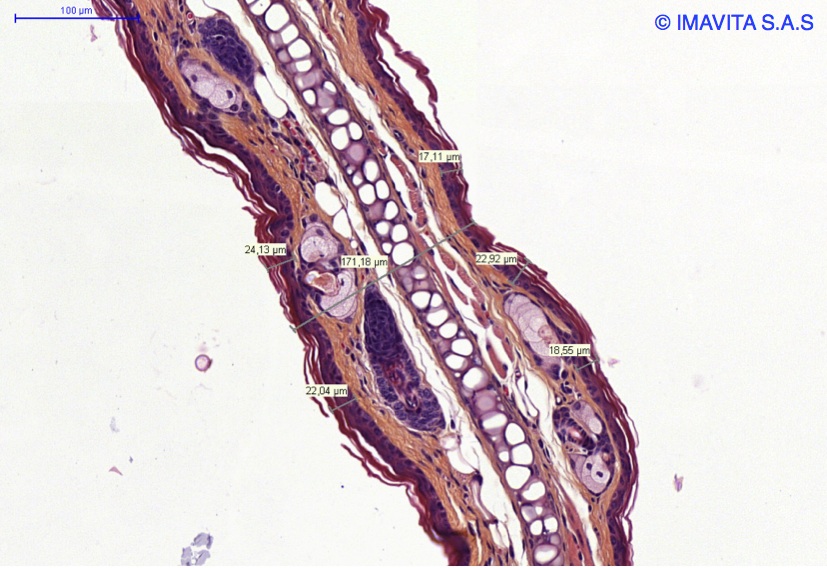

From imavita.com

Psoriasis models / Imavita / Efficacy preclinical CRO Psoriasis Model The development of relevant in vitro and in vivo models of psoriasis is now a. Chronological landmark discoveries made for human psoriasis pathogenesis are depicted in addition to the advent of individual mouse models of psoriasis. Summary of mouse models of psoriasis according to category and overlap with human psoriasis. The use of preclinical animal models of psoriasis has significantly. Psoriasis Model.